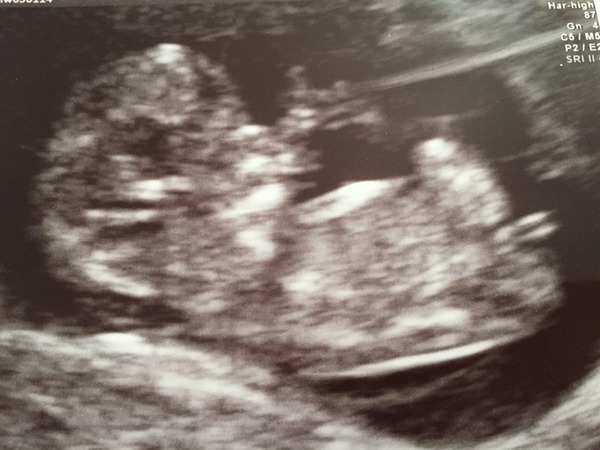

Had an NHS scan today as we were a little unsure of dates... Measuring up 10 weeks and 3 days and all looking good! Please could I be added to the Google doc?

MrsMermaid #1 EDD 26th September

So happy to see all is well! After feeling so sick for the past few weeks it has really pepped me up SmileI also can't believe it looks like a BABY. We have decided to call it 'the babe with the power' for now. Congrats to others having early scans too! Wishing you all happy sticky thoughts xx

Gorgeous scan MrsMermaid - has really put a smile on my face - congratulations!

Congratulations on those with positive scan results today. Amazing picture mermaid! It's amazing how different your scan looks compared to mine in just a weeks difference. Mine looked like a wobbly jelly bean and yours is a real baby! :)

Congrats Mermaid, that's a beautiful scan! Thanks

Wow mermaid that is a proper BABY looking baby!! Lovely.

Ah that's a fantastic scan MrsMermaid! Congrats!